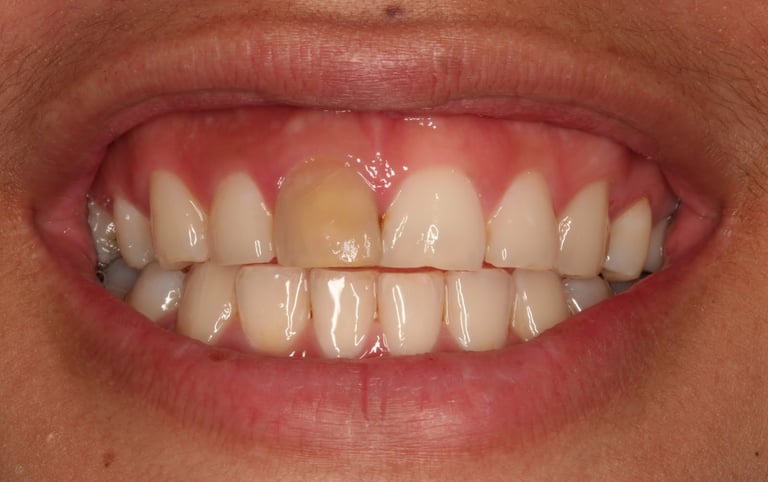

Se realiza cuando un diente se ha oscurecido debido a la muerte de la pulpa. Consiste en colocar un agente blanqueador dentro del diente para devolverle su color natural.

Blanqueamiento interno de dientes